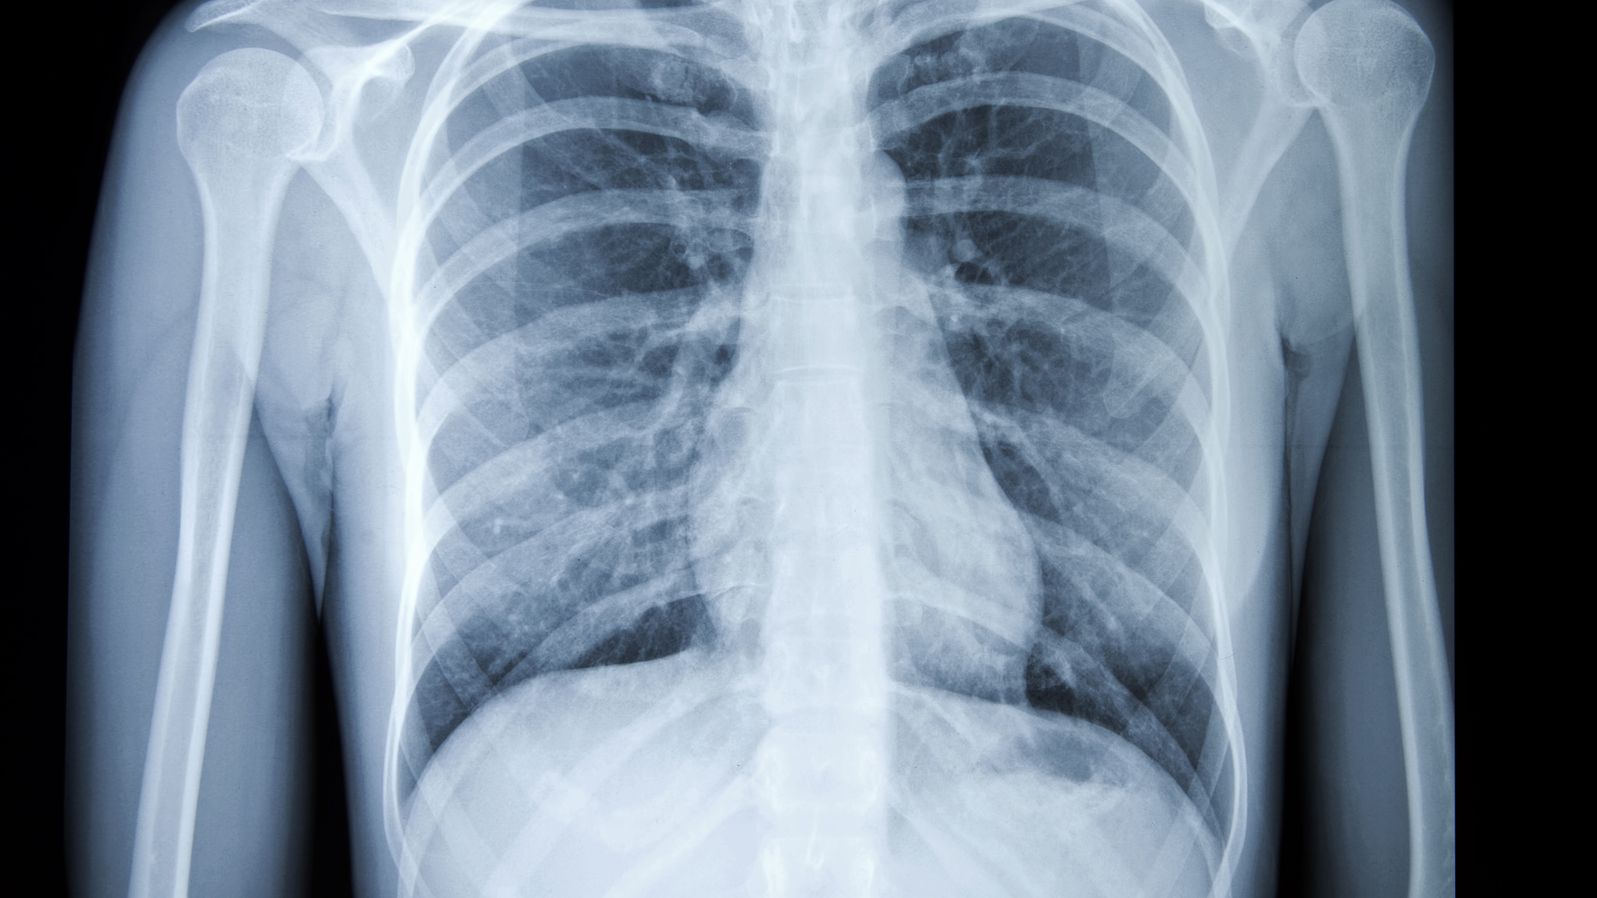

પારસ હોસ્પિટલના સ્વાન રોગ વિશેષજ્ઞ ડોક્ટર અરુણેશ કુમારના જણાવ્યા અનુસાર, જો કાર્સિનોજેનિક ગેસ નાક અથવા મોઢા દ્વારા શરીરમાં પ્રવેશ કરે છે, તો તે ફેફસાં પર ખરાબ અસર કરે છે અને તેનાથી કેન્સર ઉપરાંત અસ્થમા, બ્રોન્કાઇટિસ અને શ્વાસની તકલીફ થઈ શકે છે.